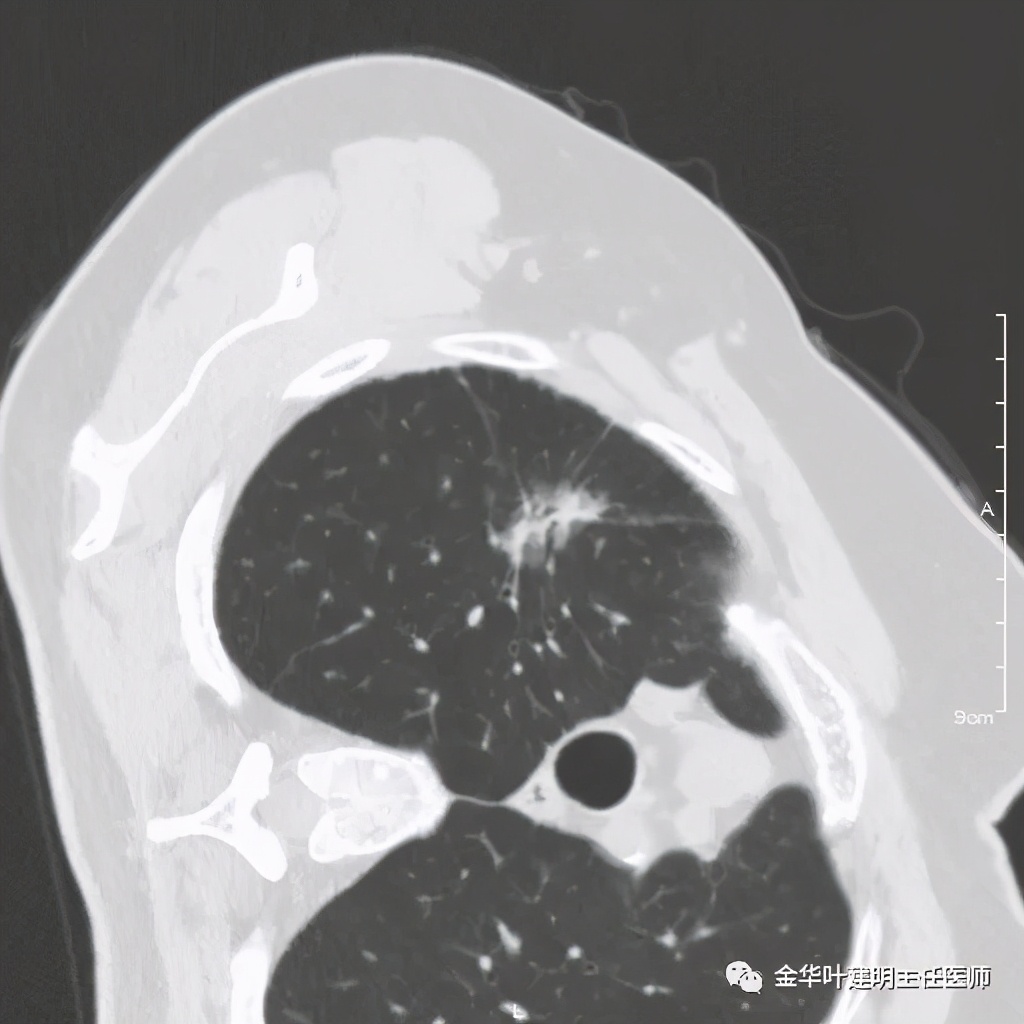

四、浸润性腺癌贴壁伴恶性度较高的实性成分:

影像特征:浸润性腺癌的贴壁生长型若伴有乳头、微乳头、实体型等成份时,更是典型的恶性的特征。此例是贴壁占60%,乳头成分占40%。我们来看其特点:桔色箭头示磨玻璃成分(代表贴壁生长部分),中央是实性成分(代表乳头生长部分),而且实性部分有收缩力(病灶向中间拉的趋势),密度高的部分又其内部密度不大均匀,毛刺也是长短不一。也就是说: 混合磨玻璃结节伴实性部分的收缩力 是其最显著的特点。实性部分若是实体型,也一般是类似表现。预后情况主要看实性成份的占比及亚型,因为贴壁成分是恶性度不高的,但若位微乳头或实体型,那便预后会差一些。也比腺泡型差。